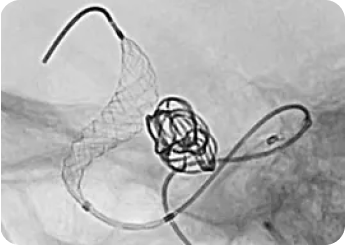

Dr. Maksim Shapiro, MD presented during a December 2025 SNIS monthly webinar, sharing a powerful case-based perspective on how device engineering, imaging, and procedural strategy intersect in real-world practice. From complex aneurysm coiling to challenging fistula and AVM cases, his emphasis on navigability, stability, and retrievability resonated throughout each case.

Dr. Adam Arthur and Dr. David Fiorella present at the 2023 SNIS conference in San Diego, California. This webinar segment discusses their early experiences with the Aristotle® Colossus wire, offering insights into the practical applications and advantages in neurovascular procedures.

This webinar originally premiered through SNIS features Aristotle® Colossus for accessing ischemic stroke as presented by Dr. Adam Arthur, Dr. Donald Frei, and Dr. David Fiorella. These expert speakers demonstrate case studies and discuss practical applications.

SNIS Webinar Dec 2022 – A18 Guidewire Applications

This SNIS webinar with Dr. Adam Arthur and Dr. Dave Fiorella focuses on the use of larger diameter wires, particularly the Aristotle® 18 in catheterizing aneurysms when paired with .021 ID catheters. They discuss considerations for its application in different scenarios.

SNIS Webinar Dec 2022 – A24 Cases

This SNIS webinar featuring Dr. Adam Arthur and Dr. David Fiorella reviews cases utilizing the Aristotle® 24 with successful outcomes. The speakers conduct a detailed discussion on thrombectomy procedures and the use of the Aristotle® 24 wire, particularly in aspiration thrombectomy cases.